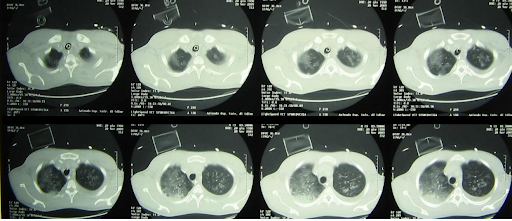

Eine Röntgenaufnahme des Brustkorbs zeigt ausgedehnte beidseitige Lungenverschattungen, die auf der rechten Seite stärker ausgeprägt sind, mit einem gemischten parenchymalen und pleuralen Muster. Vor dem Hintergrund von Fieber, Atemwegsbeschwerden und radiologischen Befunden wird die Diagnose einer schweren ambulant erworbenen Lungenentzündung gestellt. Es wird mit der intravenösen Gabe von Levofloxacin begonnen und über eine Venturi-Maske wird zusätzlicher Sauerstoff verabreicht.

ARDS_1.png

Die bei der Vorstellung durchgeführte Röntgenaufnahme des Brustkorbs zeigte beidseitige Lungeninfiltrate, die zunächst mit einer schweren ambulant erworbenen Lungenentzündung vereinbar waren.1